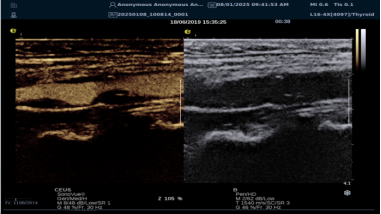

(三)mFlowTM 超微血流显像技术

mFlowTM 超微血流技术在小型机器上率先实现微米级细小血管识别与低速血流捕捉,以往仅高端台式机具备此功能。该技术专注于颈动脉粥样硬化斑块内血流评估,无需造影剂,具有高分辨率、低运动伪像和高帧频成像特点。其优势如下:

? 运用 3D 壁滤波技术智能分析信号,可探测常规超声难以捕捉的低速血流,灵敏度高。

? 依据 Staub 标准对检查结果分级,直观展示斑块内新生血管血流,为斑块稳定性评估提供新指标。

? 基于多普勒原理,进行频谱测量,并可进行VI指数测量,定量评估斑块内新生血管占比。

? 相较超声造影成像,无创便捷,为颈动脉易损斑块评估开辟新途径。

(四)iPlane Vascular 平面波超微细血流显像技术

iPlane Vascular 技术借助 OmniSound?平面波和 3D 壁滤波技术突破,提升超声多普勒分辨率并具备定量测量能力。优势如下:

? 显著提高对低速血流的敏感度,实现高分辨率、高帧频实时微血流成像(分辨率 30 微米、帧频 150 帧/s),动态显示斑块内新生血管血流。

? 基于多普勒原理进行频谱测量与 VI 指数计算,定量评估斑块内新生血管。

? 成像质量接近造影效果且无需造影剂,无创简便,增强诊断准确性,适用于细微血流变化场景。